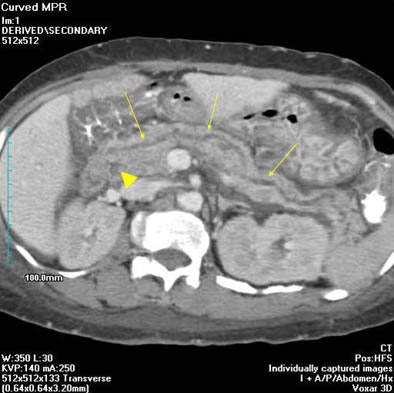

Following intravenous administration of 100 mL of intravenous contrast material (320 mg/ml iohexol at 3 ml/sec., scan delay 40-60 seconds) the radiologists acquired MDCT images of the pancreas on an MX 8000 four-row multidetector-row scanner (Philips Medical Solutions, Andover, MA) using collimation of 3.2 mm, 3-mm reconstruction intervals, 140 kVp, and mAs of 200-250. "The 2D multiplanar reformats with the curved array are actually very useful for displaying the pancreatic duct, and the curved duct can be traced quite clearly on the curved-array formats," Lucey said.

Two radiologists working independently reviewed the images on a PACS workstation, with the aid of 2D and 3D reformatting, and cine mode function. Diagnostic results and statistical measurements were calculated for each observer. The presence of the dominant dorsal duct sign was used to diagnose pancreas divisum, Lucey said.

The diagnosis was made "if we could trace the dorsal duct through the tail of the gland through the body of the gland and into the anterior aspect of the head, draining into the minor papilla...and if we could locate the ventral duct draining into the major papilla; or if the ventral duct was not seen, the caliber of the dorsal duct had to be greater than (that of) the ventral duct," he said.

| Curved MPR image shows large "dominant" dorsal duct (arrows) with smaller ventral duct posteriorly (arrowhead). Images courtesy of Dr. Brian Lucey. |

"Looking at the results from the CT perspective, in five of nine patients (diagnosed with pancreas divisum), both dorsal and ventral duct were seen, where the caliber of the dorsal duct was greater than the ventral duct," he said. "In three of the patients, the dorsal duct was seen and the ventral duct was not seen. And in one patient, the pancreatic duct was not visualized by either observer -- so that was a false negative for both observers for pancreas divisum," he said.

In conclusion, carefully performed and interpreted MDCT is highly accurate for detecting pancreas divisum -- unlike what’s been reported previously for CT, Lucey said. "The main factors responsible are the fact that you’re getting a lot of thin collimated data, and the fact that using a PACS system you can actually trace these small ductal structures. And using the curved MPRs you can lay out the pancreatic duct particularly well. For these reasons we can actually see the pancreatic duct so much better, and can see pancreas divisum so much better."